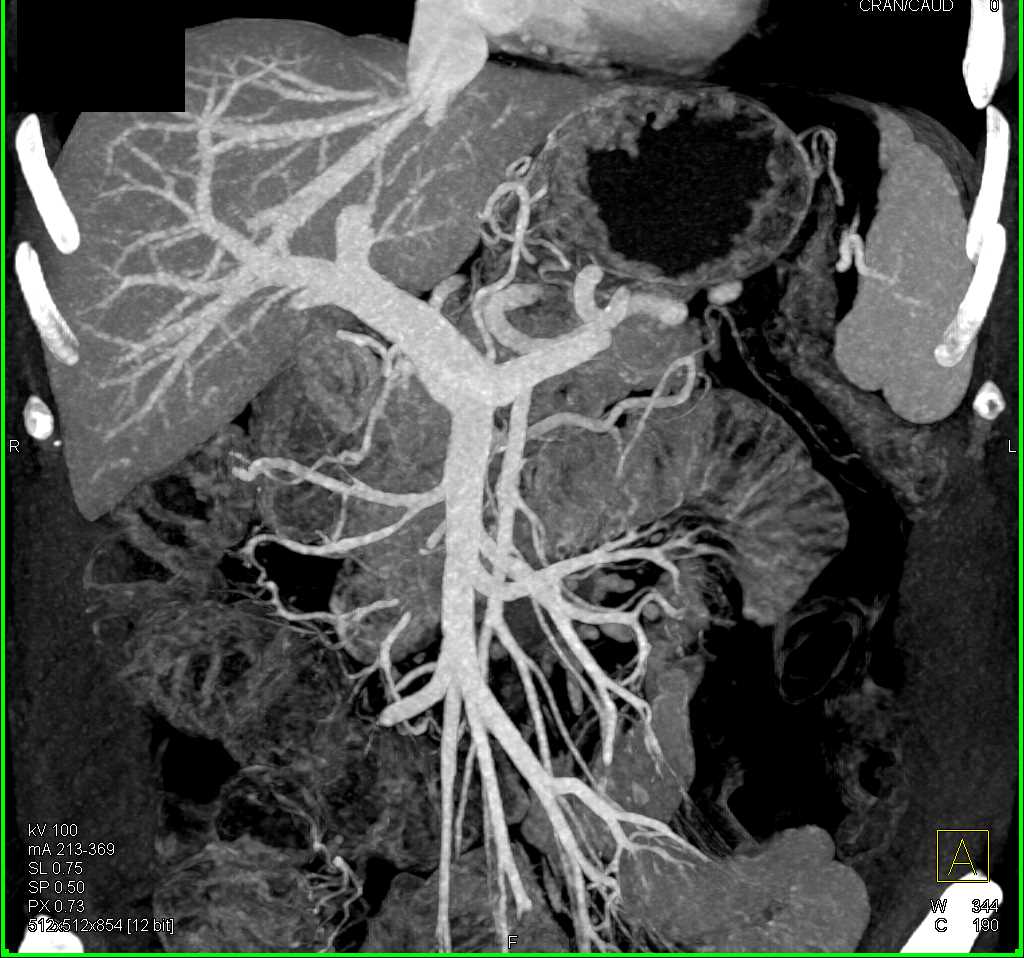

Duodenal Carcinoma with Obstruction